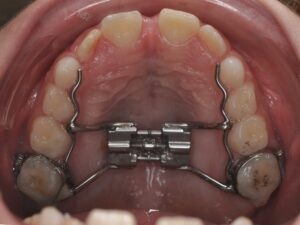

L'AXE ORTHOPÉDIQUE

Il correspond à la réorientation des croissances des mâchoires supérieures et inférieures. En effet, tant que l’enfant est encore jeune, la croissance peut être déverrouillées, voire guidée afin qu’une croissance harmonieuse des mâchoires se fasse.

Il s’agit de la mastication, la respiration, la posture linguale, les habitudes déformantes. Elles font partie intégrante de la bonne posture des mâchoires et des dents. Elles seront également contrôlées et interceptées. Les appareils sont nombreux en fonction de la malocclusion, ils peuvent être fixes ou amovibles. Très souvent, l’interception pourra être associée à un rendez-vous chez : l'ORL, l'orthophoniste, le kinésithérapeute ou encore l'osthéopathe.